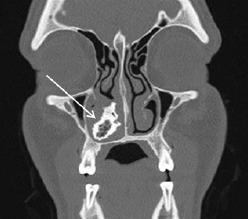

Unilateral nasal obstruction is a common complaint with a broad differential diagnosis that includes anatomic asymmetry, unilateral infective or inflammatory conditions, and benign and malignant sinonasal masses. A rhinolith is an uncommon foreign body in the nose, which serves as a nidus for calcium salt deposition. The foreign body can be endogenous or exogenous in origin and may remain asymptomatic for many years before incidental discovery. When left untreated, stones may cause unilateral nasal obstruction, rhinorrhea, nasal discharge, epistaxis or, in rare cases, progressive destruction leading to septal/palatal perforation or oro-antral fistula. Surgical removal is an effective intervention with limited complications reported.

This article describes a 34-year-old male who presented to the emergency department (ED) with unilateral obstructing nasal mass and epistaxis, which was found to be an iatrogenic rhinolith. Successful surgical removal was performed.

Epistaxis and nasal obstruction are common presentations to the ED. Rhinolith is an uncommon clinical etiology that if left undiagnosed may lead to progressive destructive disease; it should be included in the differential for any unilateral nasal symptoms of unclear origin. Appropriate work-up for any suspected rhinolith includes computed tomography, as biopsy is risky given the broad differential of unilateral nasal mass. When identified, surgical removal has a high success rate with limited complications reported.